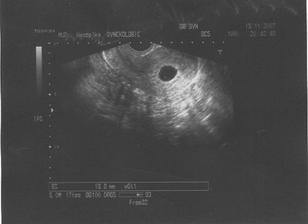

♥ 19.11.2007 - nám mudr potvrdil mimíska v bříšku, velikostí odpovídal 6t2d